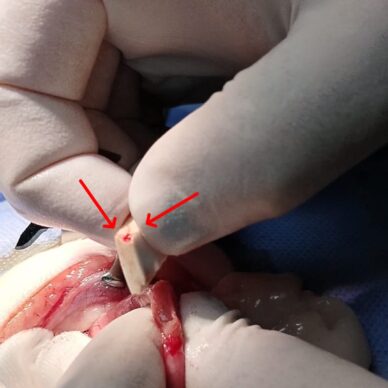

Ortopedi Cerrahi

Kedi ve köpeklerde ortopedi cerrahisinde başarı